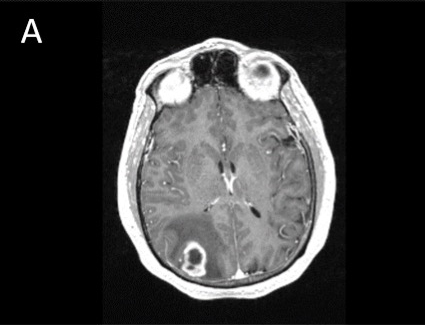

A male patient in his 50s with a remote medical history of Guillain-Barre, left parietal infarct and seizure disorder, renal cell carcinoma, presented in the ED with altered mental status with associated confusion and somnolence in June 2015. MRI found a 2.5cm rim enhancing right parietal solitary mass with associated edema and possible central necrosis (Figure 1A). Patient underwent craniotomy for tumor resection. Pathology was of a glioblastoma. In house immunostains (IHC) showed negativity of Isocitrate dehydrogenase 1 (IDH1) mutations and high percent of MGMT staining. FISH showed no EGFR amplification.

A. T1-post contrast MRI showing a right parietal, rim-enhancing lesion. B. H&E of the tumor showing endothelial proliferation with palisading necrosis C. ALK positively in ~5% of tumor cells.

Glioblastoma is the most frequent malignant brain tumor in adults, accounting for approximately 40-50% of all primary malignant tumors in the brain. The tumor most often centered in the subcortical white matter and deeper grey matter of the cerebral hemispheres. On imaging study, glioblastomas are irregularly shaped and have a ring-shaped zone of contrast enhancement around central area of necrosis. Typical pathologic features include prominent microvascular proliferation and palisading necrosis.